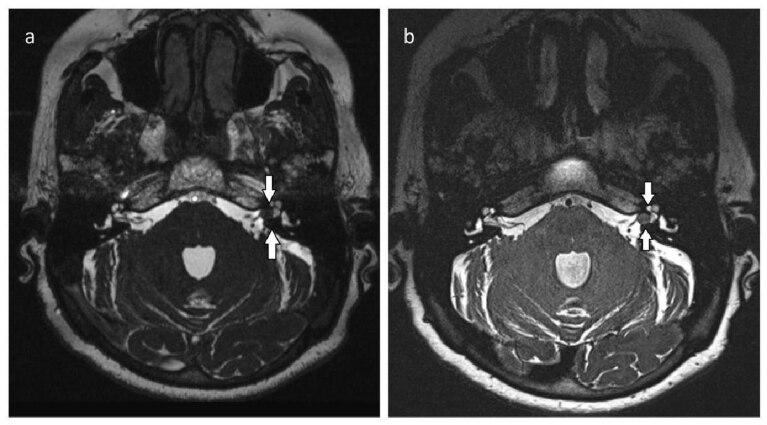

Evaluation of schwannoma using the 3D-SPACE sequence: comparison with the 3D-CISS sequence in 3T-MRI.

BACKGROUND/AIM: The purpose of this study is to compare the diagnostic accuracy and interobserver reliability of the T2-weighted 3D-SPACE (three-dimensional sampling perfection with application-optimized contrasts by using different flip angle evolutions) sequence in comparison with T2-weighted 3D-CISS (three-dimensional constructive interference in steady state) sequences for diagnosis of schwannomas.

The interobserver agreement was found to be excellent between the two observers for the interpretation of all qualitative analyses for both sequences (kappa value > 0.8). The 3D-SPACE sequences demonstrated significantly better qualitative scores and fewer artifacts compared with the 3D-CISS sequences (p < 0.05).

Our results demonstrate that 3D-SPACE is superior to 3D-CISS in the imaging process of the schwannoma in terms of image quality, description of the relationship between the lesion and cranial nerve, signal differentiation between lesion and cistern, and signal differentiation between the lesion and adjacent brain.